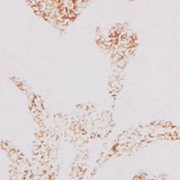

Aerie Printed Binding Bikini Bottom

Mix & match with your fave bikini top styles!